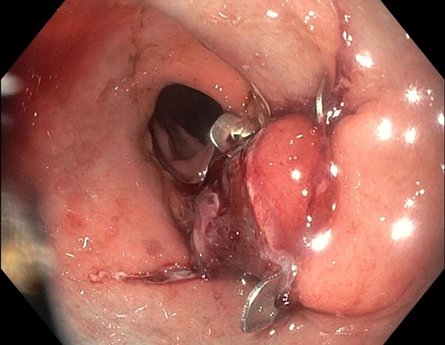

Statt einer erneuten Operation kann in vielen Fällen heute ein schonendes endoskopisches Verfahren eingesetzt werden. Dabei erfolgt die Behandlung von innen, also über eine Magenspiegelung – ganz ohne Bauchschnitt. In diesem Fall wurde eine endoskopische Verkleinerung der Anastomose mit dem BARS™-System (Ovesco) durchgeführt. Der Eingriff dauert in der Regel nur kurze Zeit, erfolgt meist in Sedierung und erfordert keinen längeren Krankenhausaufenthalt.

Bild 2: Verkleinerte Anastomose nach endoskopischer Therapie